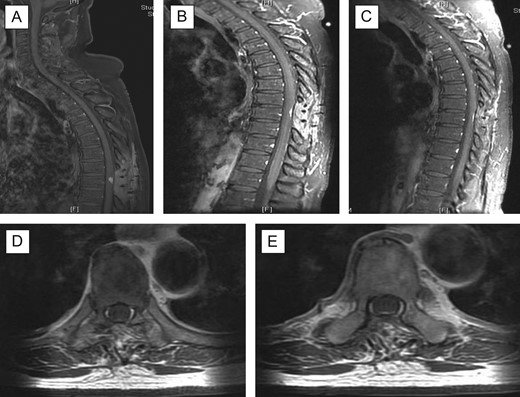

The histopathology sections (Fig. 3) showed hypercellular areas containing a proliferation of spindle cells arranged in a vague storiform-like pattern, present around numerous small calibre and ectatic blood vessels. The cells had bland ovoid to round nuclei, eosinophilic cytoplasm with indistinct cell borders. Looser myxoid stroma was seen in the hypocellular areas. There were no mitoses, necrosis or areas of marked hypercellularity. Reticulin highlighted the vascular pattern. On immunohistochemical staining, the spindle cells were diffusely positive for vimentin and focally positive for Factor 13a. CD34 highlighted the vasculature and showed scattered positive intervening cells. They were negative for EMA and S100 protein. A diagnosis of HPC (WHO Grade II) was made.

(A) (CD34X40): patchy CD34 immunoreactivity in tumour cells and endothelial cells; (B) (FXIIIAX40): focal FXIIIa positivity in tumour cells; (C) (HEX10): highly vascular spindle cell tumour with numerous slit like and staghorn vascular spaces, featuring hypocellular and cellular areas; (D) (HEX40): closely packed randomly oriented bland spindle cells; and (E) (RETICULINX40): well-developed network of reticulin fibres surrounding individual cells.